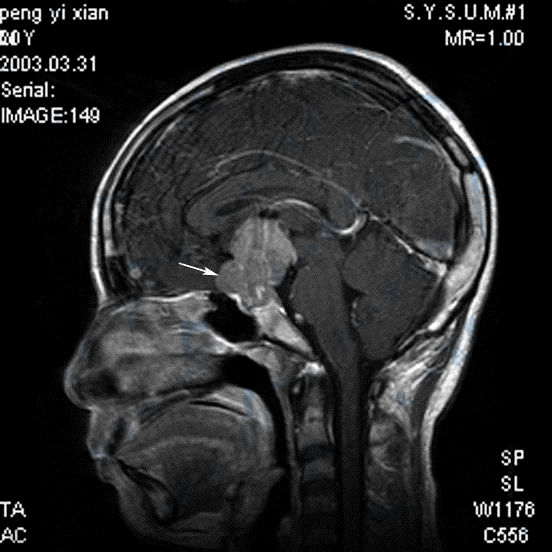

性腺功能减退:生殖细胞瘤的MRI磁共振成像

是起源于胚胎早期移行生殖细胞残遗的恶性肿瘤,是胚细胞瘤,多发生于青少年。最常见的部位是松果体区,其次为鞍上区。临床主要症状有:①颅内压增高:系肿瘤压迫中脑导水管所致;②邻近